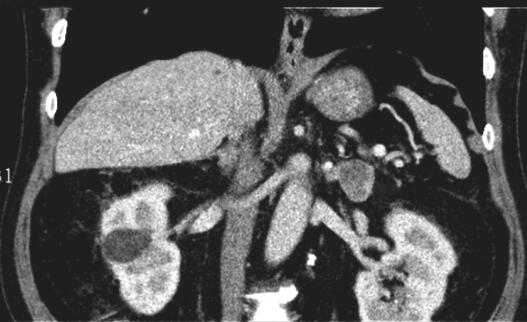

双侧肾上腺CT扫描示:双侧肾上腺区类圆形低密度影,与双侧肾上腺外支分界不清(图1)。双侧肾上腺增强CT扫描:双侧肾上腺区类圆形占位,肿瘤性病变可能:转移瘤?腺瘤?(图2,图3)。

图3 双肾及肾上腺增强CT(冠状位):CT示双侧肾上腺腺瘤(箭头标注处)

计算患者的ARR(血浆醛固酮/肾素活性比值,plasma aldosterone-renin ratio)为40.54,立卧位实验显示立位醛固酮水平不升高反而降低,结合其双侧肾上腺CT结果,考虑为醛固酮腺瘤(双侧)。患者及家属考虑患者高龄,不愿行醛固酮腺瘤切除术,予以药物保守治疗,醛固酮受体拮抗剂螺内酯40mg,1次/日,硝苯地平控制片30mg,1次/日。